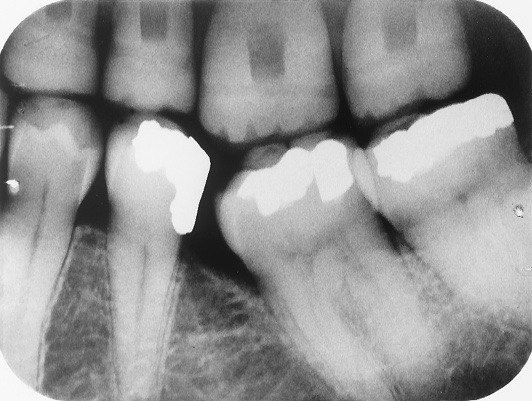

13. What condition can be seen on the teeth # 4.4 and 4.5?

14 / 30

14. What condition can be seen on the root surface of tooth # 1.1.?

15 / 30